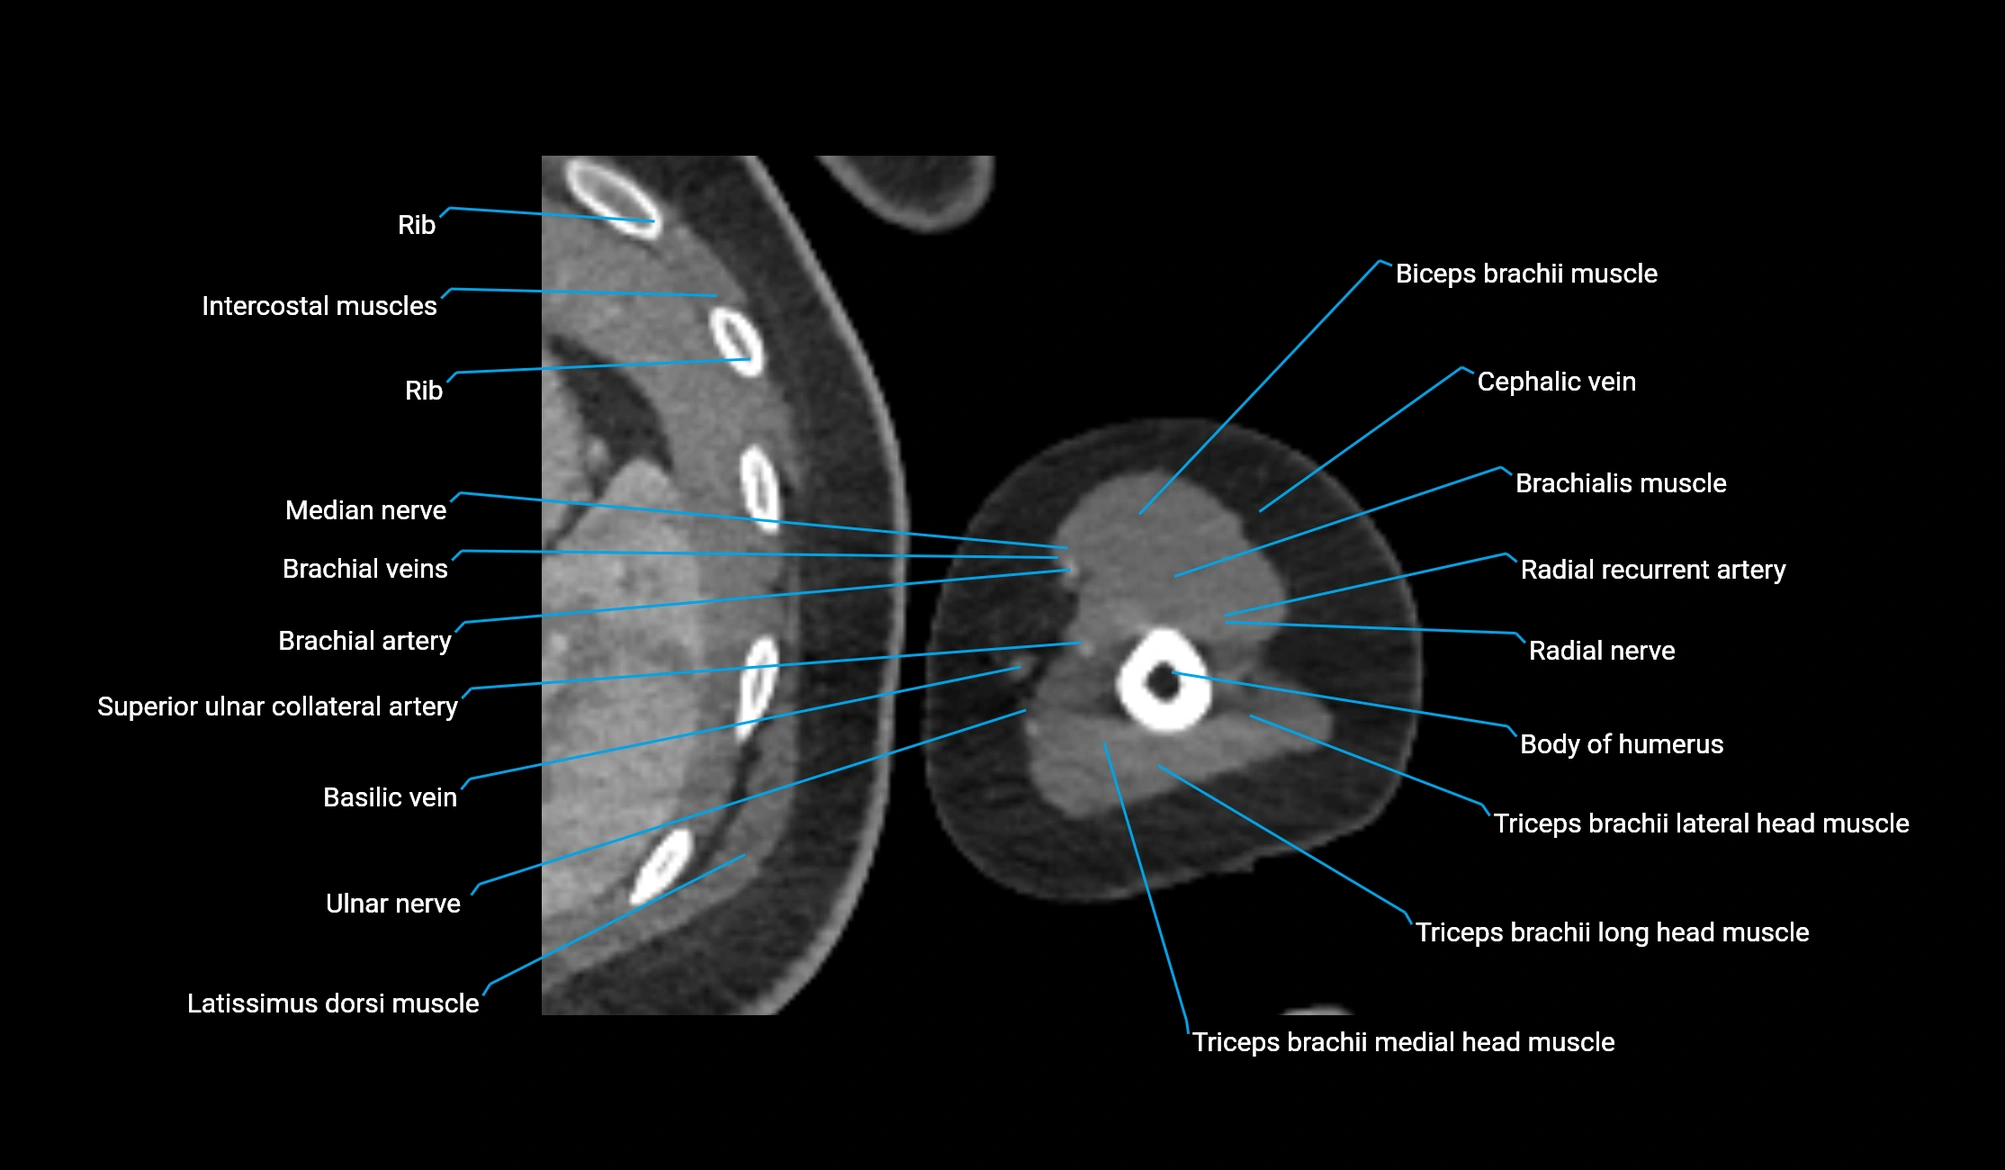

- Body of humerus

- Brachial artery

- Brachialis muscle

- Cephalic vein

- Long head of triceps brachii muscle

- Medial head of triceps brachii muscle

- Median nerve

- Radial nerve

- Radial recurrent artery

- Superior ulnar collateral artery

- Triceps brachii muscle

- Ulnar nerve